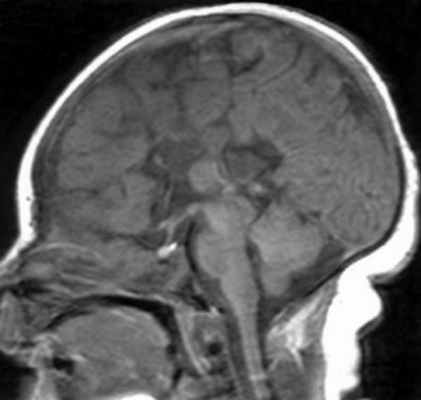

• Гипертрофированное БВ часто имеет гиперинтенсивный сигнал на T2-ВИ/FLAIR (ускоренная миелинизация)(а) На рисунке коронального среза показано увеличение объема большого полушария головного мозга вследствие его чрезмерного роста. Обратите внимание на смещение срединных структур, избыточное количество белого вещества (БВ), утолщение и сглаженность/дисморфизм извилин, а также аномальную конфигурацию ипсилатерального переднего рога.

(б) Бесконтрастная КТ, аксиальный срез: у четырехлетней девочки с некупируемым судорожным синдромом определяется увеличение правого большого полушария, ипсилатеральной 1 /2 мозгового черепа в сочетании с увеличением объема белого вещества лучистого венца, ипсилатерального мозолистого тела, а также свода мозга. Кроме того, отмечается латеральное смещение серпа мозга. (а) МРТ, Т2-ВИ, аксиальный срез: у того же пациента определяется увеличение размеров полушария в сочетании с повышением сигнала от его БВ, а также увеличение деформированного правого желудочка и утолщение диспластичной коры.

(б) МРТ, Т2-ВИ, корональный срез: определяются увеличение размеров правого полушария, а также латеральное смещение серпа мозга. Передний рог ипсилатерального бокового желудочка деформирован и заострен. Изменения соответствуют классической гемимегалэнцефалии (ГМЭ).в) Патология:

Гемимегалэнцефалия (ГМЭ) или унилатеральная мегалэнцефалия — дисплазия головного мозга, обусловленная унилатеральными нарушениями нейронной миграции и пролиферации, результатами которых является одностороннее диспластическое увеличение одной из гемисфер (В.А. Чадаев и соавт., 2003). Гемимегалэнцефалия может встречаться как изолированный порок, так и сочетаться с гемигипертрофией всего тела — синдром Клиппель-Треноне-Вебера (Anlar B. и соавт., 1988); нейрокожными синдромами: протеуса, линейного невуса, эпидермального невуса, гипомеланоза Ито, нейрофиброматоза, туберозного склероза (De Lone D.R. и соавт., 1999; Sasaki M. и соавт., 2000).

Облигатным признаком ГМЭ является чрезмерное развитие одной гемисферы при нормальных размерах другой. Нарушение устройства рисунка извилин (сулькации) может быть представлено участками коры с увеличенными, утолщенными (пахигирия) или удлиненными и истонченными (полимикрогирия) зонами. В гипертрофию обычно вовлекаются глубинные структуры полушарий, реже мозжечок. Гемигипертрофия ствола мозга или спинного мозга является редкостью (Tuxhorn I. и соавт., 1997). Диспластические нарушения могут обнаруживаться и в контралатеральном «здоровом» полушарии.

Диагноз ГМЭ в современных условиях устанавливается, в подавляющем большинстве случаев, при МРТ исследовании головного мозга. МРТ у больных с ГМЭ выявляет асимметрию гемисфер за счет диффузно увеличенного, аномального полушария. Характерна вентрикуломегалия диспластичной гемисферы. В Т2 — режиме выявляется интенсивный сигнал в белом веществе — результат сочетания глиоза и участков гипомиелинизации.Материал и методы. Нами обследовано 4 больных ГМЭ в возрасте от 5 до 7 лет; 2 мальчика и 2 девочки (табл. ). Проводилось неврологическое обследование, рутинная ЭЭГ, видео – ЭЭГ мониторинг с включением сна (6-12 часов исследования), магнитно – резонансная томография (МРТ) с напряженностью поля 1,5 Tsl. Целью исследования было изучение клинических, электроэнцефалографических и нейровизуализационных характеристик больных гемимегалэнцефалией. Особое внимание уделялось характеристики симптоматической фокальной эпилепсии при ГМЭ: возраст дебюта приступов, их характеристика, динамика течения.

МРТ исследование было ведущим в верификации синдрома ГМЭ.